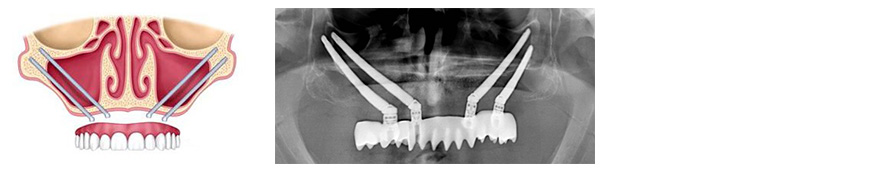

Existen casos de atrofia maxilar tan severa que no es posible la colocación de implantes orales convencionales. En estos las únicas alternativas son la realización de injertos de hueso de origen extraoral o la colocación de implantes zygomaticos anclados en el hueso malar. Con estos implantes rehabilitamos de manera fija el maxilar en solo 24 horas y en una sola cirugía. No dude en consutarnos y le realizaremos el estudio de su caso sin ningún compromiso y de manera gratuita.